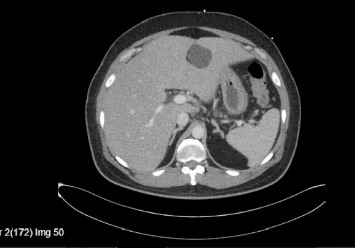

背景:伤寒是一种由伤寒沙门菌和副伤寒沙门菌引起的多系统疾病,可通过受污染的水和食物经粪便经口传播。在美国,这是一种罕见的诊断,大多数病例报告发生在返回的旅行者身上。肝炎和胆汁淤积是沙门氏菌感染的罕见后遗症。然而,急性肝衰竭(ALF)是非常罕见的。我们报告一例伤寒在返回旅行者到美国进展到ALF。病例介绍:一名48岁男性,表现为高热、腹痛、呕吐、胆汁性便、尿色深、皮肤和巩膜变黄,持续一周。他对甲型和乙型肝炎有免疫力,近期用药也没有变化。他没有饮酒史。就诊时,患者心动过速,但血流灌注良好,伴有弥漫性腹部压痛。实验室结果显示白细胞增多,肌酐升高,肝酶升高的混合肝细胞和胆汁淤积模式,氨水平升高,溶血参数阴性。病毒性、自身免疫性和代谢性肝炎均为阴性。腹部超声显示胆道系统正常,腹部CT显示多发肝囊肿,肠系膜及肝门淋巴结病变,回肠末端轻度增厚。开始静脉注射头孢曲松和甲硝唑。血液培养培养出伤寒沙门氏菌。患者临床病情恶化,出现精神状态改变、呼吸窘迫,终末期肝病(MELD)评分呈上升趋势,并被升级至重症监护病房。开始静脉滴注美罗培南,临床恢复,重复血培养阴性。患者完成2周美罗培南治疗后出院。结论:伤寒可引起危及生命的肝功能衰竭,但罕见。临床医生应该意识到这一点,因为它的进展迅速,临床病程危及生命,而且耐多药和广泛耐药伤寒的增加导致开始使用正确抗生素的延误。

Background: Typhoid fever is a multisystemic illness caused by Salmonella typhi and Salmonella paratyphi, transmitted fecal orally through contaminated water and food. It is a rare diagnosis in the US, with most cases reported in returning travelers. Hepatitis and cholestasis are rare sequelae of salmonella infection. However, acute liver failure (ALF) is exceptionally uncommon. We report a case of typhoid fever in a returning traveler to the US progressing to ALF. Case Presentation: A 48-year-old man presented with high-grade fever, abdominal pain, vomiting, acholic stools, dark urine, and yellowish discoloration of skin and sclera for one week. He was immune to hepatitis A and B, with no recent change in medications. He had no history of alcohol consumption. On presentation, the patient was tachycardic but well perfused with diffuse abdominal tenderness. Laboratory results showed leukocytosis, elevated creatinine, mixed hepatocellular and cholestatic pattern of raised liver enzymes, elevated ammonia levels, and negative hemolytic parameters. Viral, autoimmune, and metabolic causes of hepatitis were negative. Ultrasound of the abdomen revealed a normal biliary system and a computerized tomography (CT) scan of the abdomen showed multiple liver cysts, mesenteric and porta-hepatis lymphadenopathy, and mild thickening of the terminal ileum. Intravenous (IV) ceftriaxone and metronidazole were initiated. Blood cultures grew S. typhi. The patient clinically deteriorated and developed altered mental status, respiratory distress, and an up-trending Model for End-Stage Liver Disease (MELD) score and was upgraded to the intensive care unit. IV meropenem was initiated, resulting in clinical recovery and negative repeat blood cultures. The patient completed 2 weeks of meropenem and was discharged. Conclusion: Typhoid fever can cause life-threatening liver failure which is rare. Clinicians should be aware of this due to the rapid progression and life-threatening clinical course, as well as the rise of multidrug-resistant and extensively drug-resistant typhoid causing delays in starting the right antibiotic.